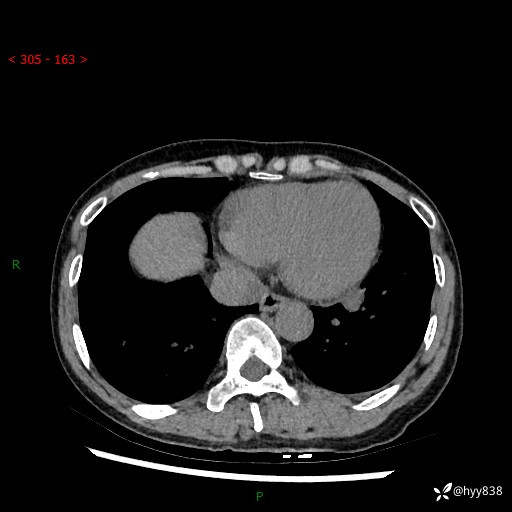

【患者信息】:55岁/女

【主诉】:咳嗽咳痰半月,发现肺占位2天

【现病史及既往史】:患者半月前出现咳嗽咳痰,伴头晕胸闷、无发热气喘。于当地医院住院行抗感染治疗1周(具体药物不详),后咳嗽减轻,但仍未完全缓解,复查胸部CT示:左肺下叶1.8*1.2结节软组织影。为求进一步诊治来我院,门诊以“肺占位”收入院。 自患病以来,精神、饮食、睡眠尚可,大小便正常,体力体重无明显减少。

【检查】:胸部CT平扫+增强

各期CT值:40hu 57hu 49hu